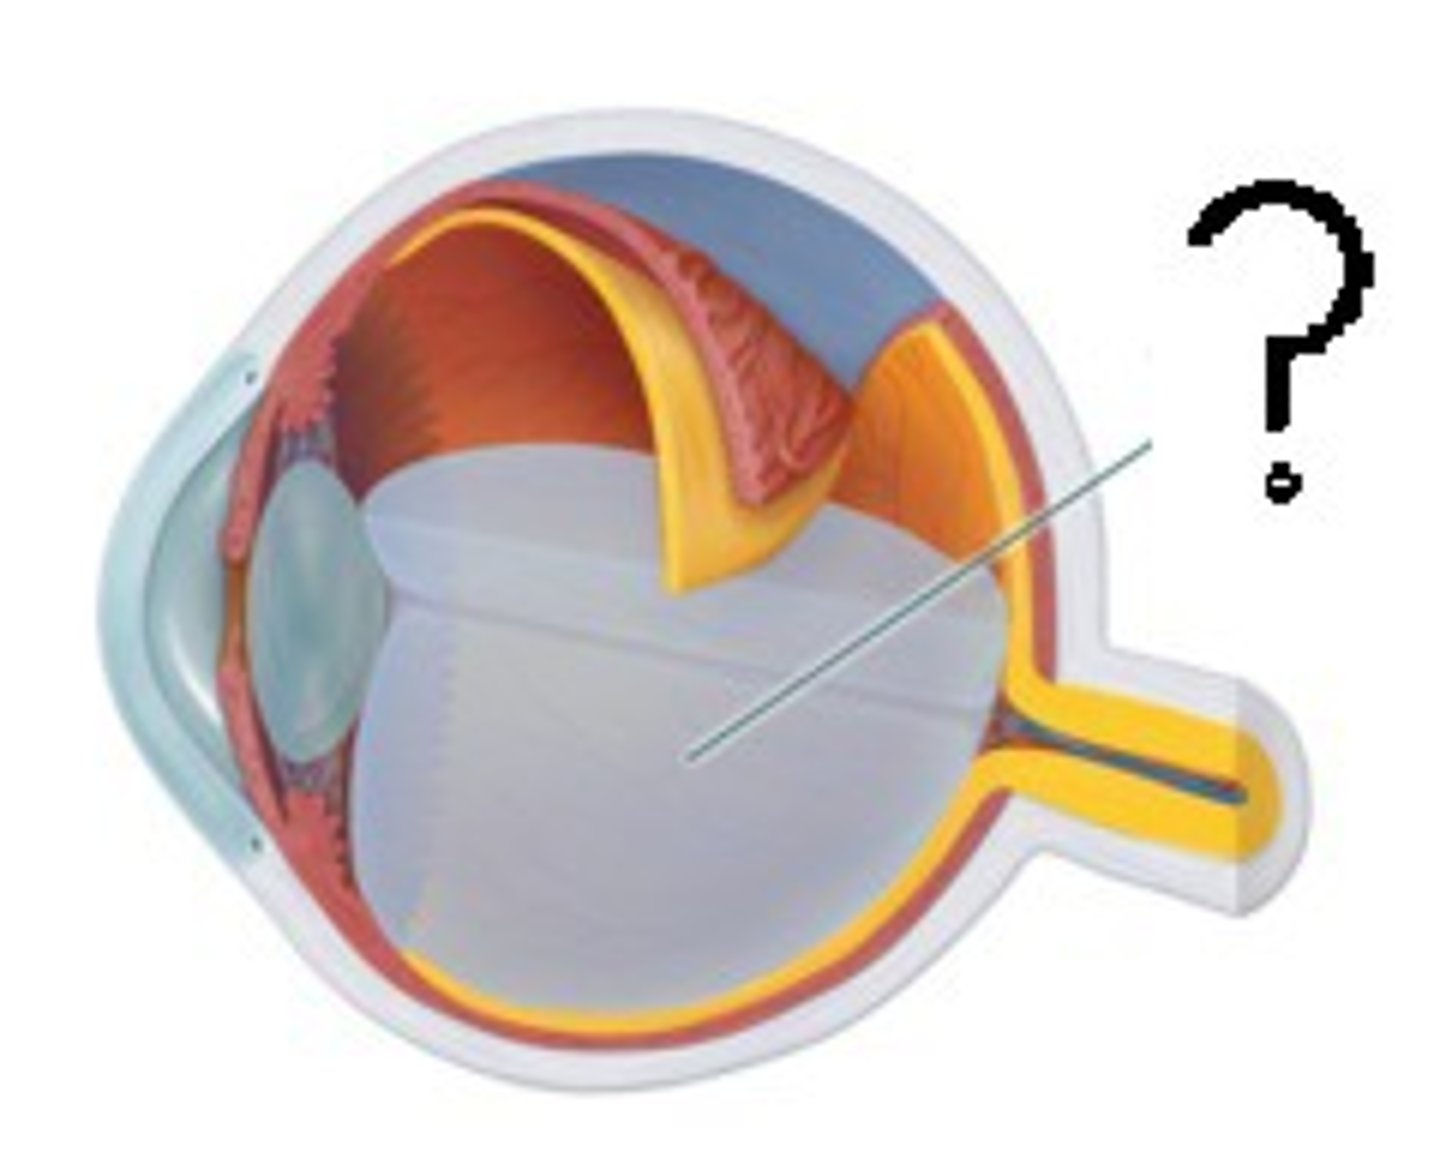

anterior cavity (of eye)

iris

B

optic disk (blind spot)

choroid

L

ciliary body

B

ciliary process

conjunctiva

cornea

D

fovea centralis

suspensory ligaments

C

vitreous humor

lens

H

macula lutea

nasolacrimal duct

lacrimal gland

posterior cavity (of eye)

pupil

F

retina

M

sclera

optic nerve